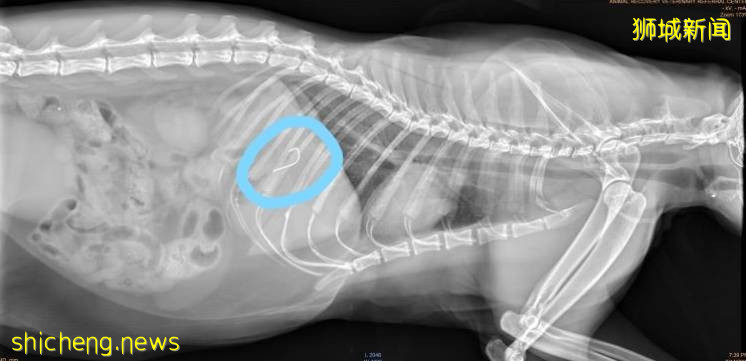

圣约翰岛上社区的一只猫最近接受了一项手术,目的是从其胃中去除鱼钩。

王子立即在主岛上等待,并进行了2小时的手术,以摘出嵌在其胃壁上的鱼钩。

根据帖子中的一张照片,钩子长约1.5厘米。

根据该帖子,钩子首先被发现在猫的嘴里,然后才进入王子的肚子。

钩子刺穿了猫的牙龈,并进入其胃中,但钩子并未刺穿猫的胃。

兽医通过内窥镜检查成功地将钩子从动物恢复兽医转诊中心的叶凯莉博士和黄宏博士那里移除。

钩子很困难地从猫的胃的顶角移开,并轻轻地移开,不会对猫科动物造成任何进一步的伤害。